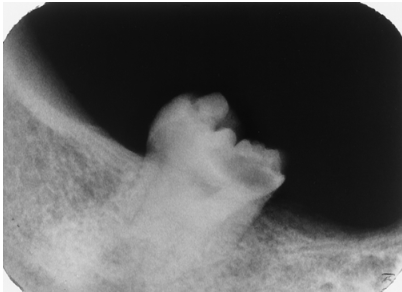

This tooth has a carious lesion, is broken down, and the dentist is contemplating extraction. Which one factor seen here is MOST likely to complicate the extraction?

ankylosis